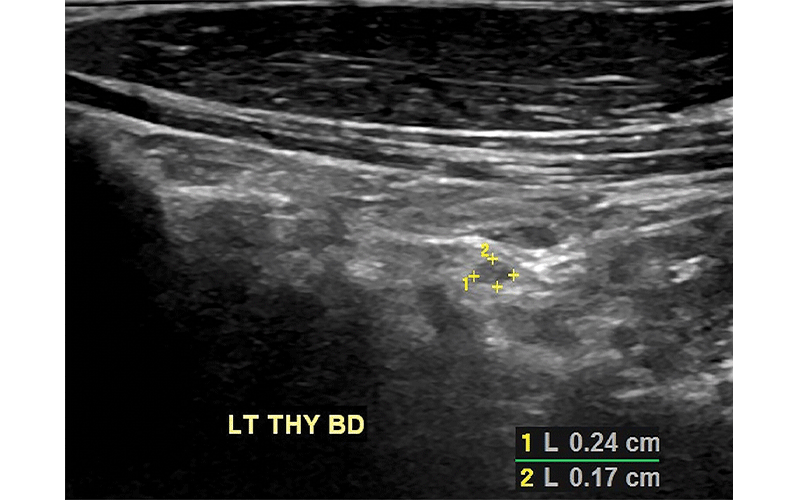

Ultrasound scans of the left thyroid bed (LT THY BD) in a 57-year-old man with history of tall cell variant of papillary thyroid cancer. (a) Sagittal scan shows a 2.4-mm × 1.7-mm solid mass. (b) Transverse scan of the same mass measuring 2.4 mm. This lesion was too small to sample with fine-needle aspiration biopsy but was stable for 5 years and presumed benign.

Frates et al, Radiology 2021© RSNA 2021